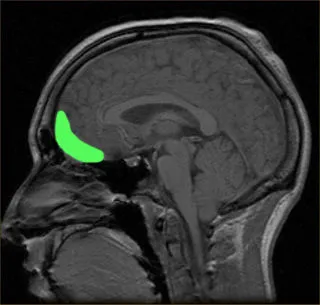

과학적으로 증명된 여러 연구에서 지속적인 명상은 안와전두엽(orbitofrontal cortex)과 전측대상회(anterior cingulate cortex)를 활성화시켜 통증을 감소시킨다. 이는 통증에 대한 자기통제와 관련 있는 영역이다. 또한 마음챙김 명상은 감각정보를 상위 뇌에 전달하는 관문 역할을 하는 시상을 비활성화한다. 그래서 통증을 느끼는 정도를 다르게 할 수 있다는 의미다. 즉 명상은 통증을 직접적으로 조절하는 능력을 향상시키고 감각정보가 통증을 인식하는 정도를 조절할 수 있도록 뇌를 적합하게 변화시킨다는 의미다.

OrbitoFrontalCortex_Optimism_Wikimedia_0.jpg?itok=ej4VGCNG 안와전두엽: 녹색부분Source: Wikimedia Commons/Public Domain